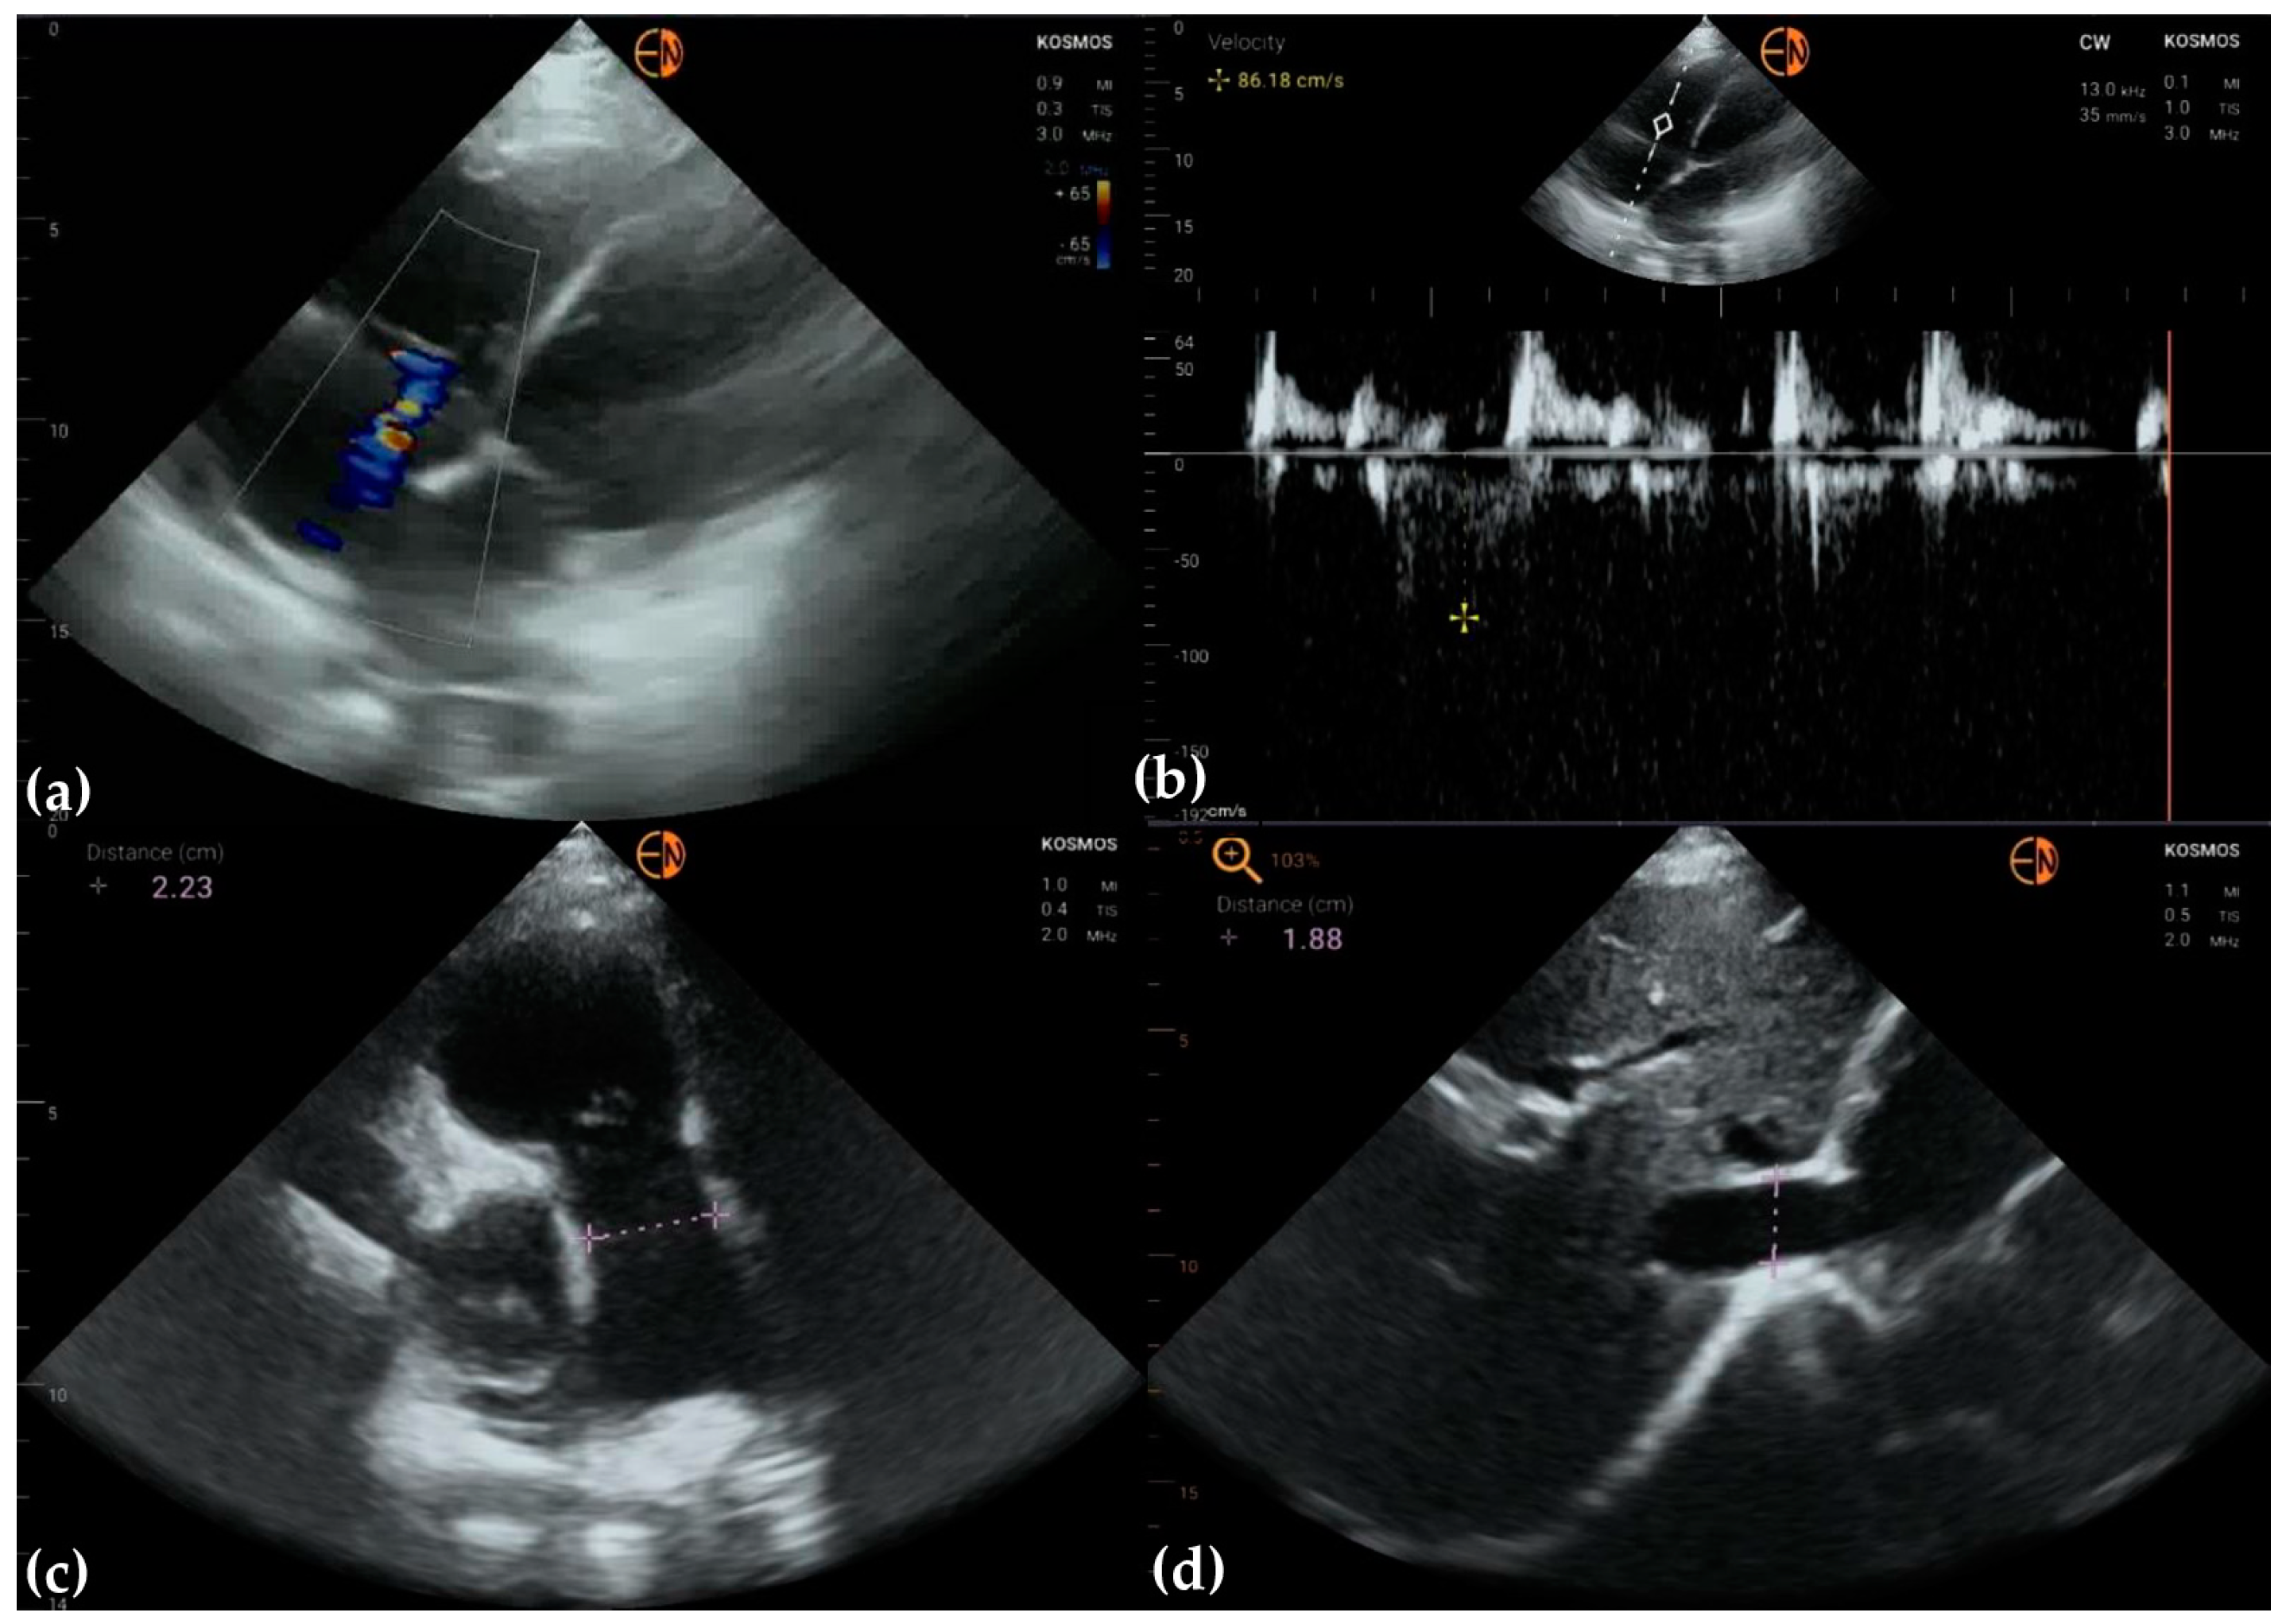

3.3. Valvular Stenosis and Regurgitation

| Tricuspid valve | 29 (69.0 [52.8 to 81.9]) 0.6072 [0.4183 to 0.7961] | ||

| Mild tricuspid regurgitation | 12 | 11 | |

| Moderate tricuspid regurgitation | 7 | 5 | |

| Severe tricuspid regurgitation | 3 | 1 | |

| Normal | 20 | 25 |